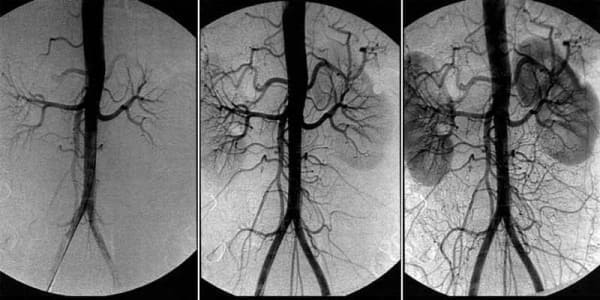

Az agyi erek vérellátásának helyreállítása érdekében az egész test vérereit meg kell tisztítani a felhalmozódott szennyeződésektől, koleszterin lepedéktől, vérrögöktől és kalcium-lerakódástól.

Mindezek a problémák - következmények. Az agyi vérkeringés károsodásának következményei, az erek koleszterinplakkokkal és vérrögökkel való szennyeződése. De polgáraink közül szó szerint kevesen figyelnek az érrendszeri tisztításra, évekig szenvednek, és haszontalan készítményeket szednek krónikus patológiáikra.

— A problémák csak súlyosbodni fognak. Igen, ezeket el lehet "tompítani" különféle eszközökkel, akár műtéthez is folyamodhat, de az ok nem fog eltűnni.

És minél több szennyeződés halmozódik fel az erekben, annál súlyosabbak lesznek a következmények. A közepes vagy súlyos agyi érszennyezés nagyobb valószínűséggel vezet agyvérzéshez és teljes vagy részleges bénuláshoz .